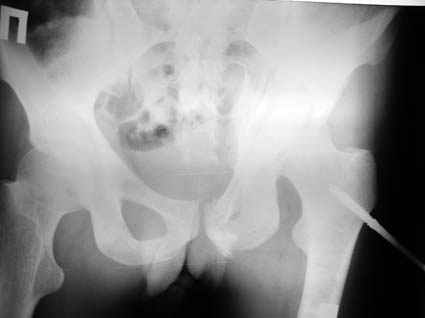

Все-таки надо бы начать не с КТ, а с обзорного снимка таза и косых проекций впадины.

Это обзорные и косые снимки